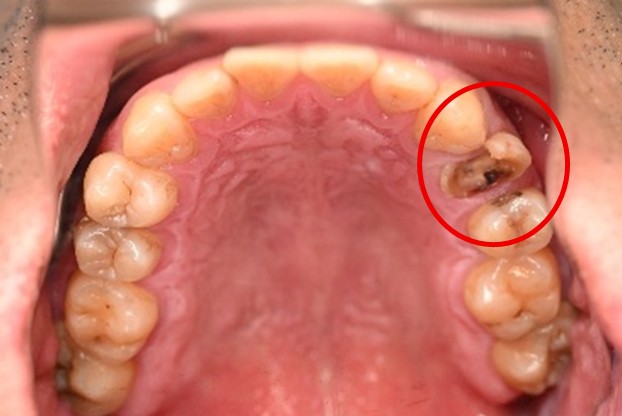

女性 Mさん 40代 (オールセラミック冠)

主訴

上の前歯が欠けた。

治療内容

神経をとる治療をし、根管治療後、ファイバーコアを入れ、オールセラミック冠を被せました。

所感

右前歯がむし歯で大きくかけていました。レントゲンを撮り詳しく診てみると、むし歯が深く、神経をとる治療が必要なことがわかりました。被せ物は、メタルフリーの治療を希望されましたので、ファイバーコアを入れオールセラミック冠を被せました。右上にむし歯があります。今後、そこの部分に取り組んでいきます。

オールセラミック冠1本:¥104,500(税込)

Before

むし歯が深く、神経に到達するむし歯でしたので、根管治療をしました。